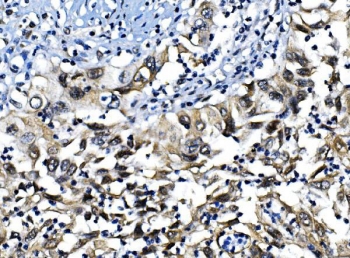

Interferon regulatory factor 1, also known as MAR is a protein that in humans is encoded by the IRF1 gene. The IRF1 gene is mapped to chromosome 5q31.1 by pulsed-field gel electrophoresis. IRF1 encodes interferon regulatory factor 1, a member of the interferon regulatory transcription factor (IRF) family. IRF1 serves as an activator of interferons alpha and beta transcription, and in mouse it has been shown to be required for double-stranded RNA induction of these genes. IRF1 also functions as a transcription activator of genes induced by interferons alpha, beta, and gamma. Further, IRF1 has been shown to play roles in regulating apoptosis and tumor-suppressoion.

Recombinant human protein (amino acids M170-L315) was used as the immunogen for the IRF-1 antibody.